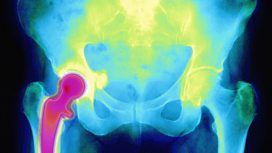

Medical: Osteoporosis

What is the best way to manage fragile bones?